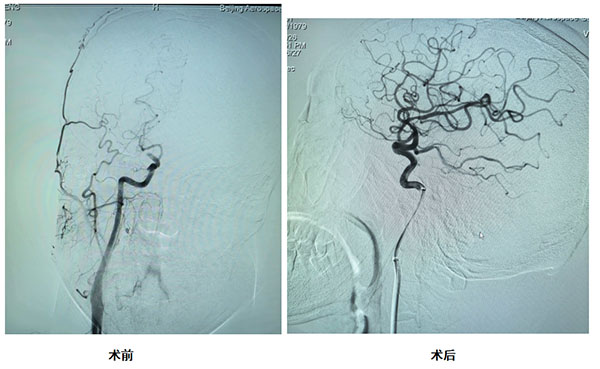

同一天,另一位患者为46岁男性,在长途久坐后,扔垃圾时突然倒地。入院时左侧肢体完全瘫痪、双眼向右凝视、言语含糊不清,确诊为大血管闭塞性脑卒中。我院神经内科团队立即启动静脉溶栓桥接动脉取栓,通过介入手术成功取出大脑中动脉血栓。DPT时间仅70分钟。术后患者双眼凝视消失,左侧肢体肌力恢复至5级,言语流利清晰,转危为安。